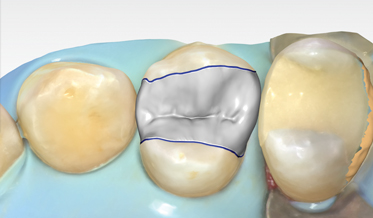

In-Office CAD/CAM Coronal Treatment With Lithium Disilicate Achieved in Efficient, Predictable Manner

Digital Workflow as an Aid to Complex Multidiscipline Dental Treatment for Improved Esthetics

Fred A. Puccio, DDS; and Gregori M. Kurtzman, DDS